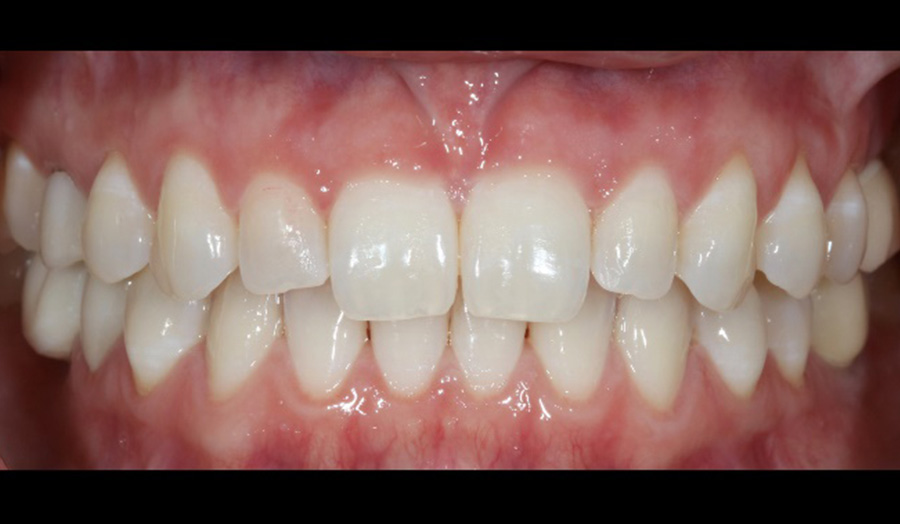

A 47-year-old female presented to my office with concerns about six anterior zirconia crowns recently done at another office. The efficiency and ease of use of the Primeprint Solution allows me to quickly print models on the same day of treatment which enables me to present a preview of treatment to patient before the final production with CEREC Primemill.

After: Final restoration